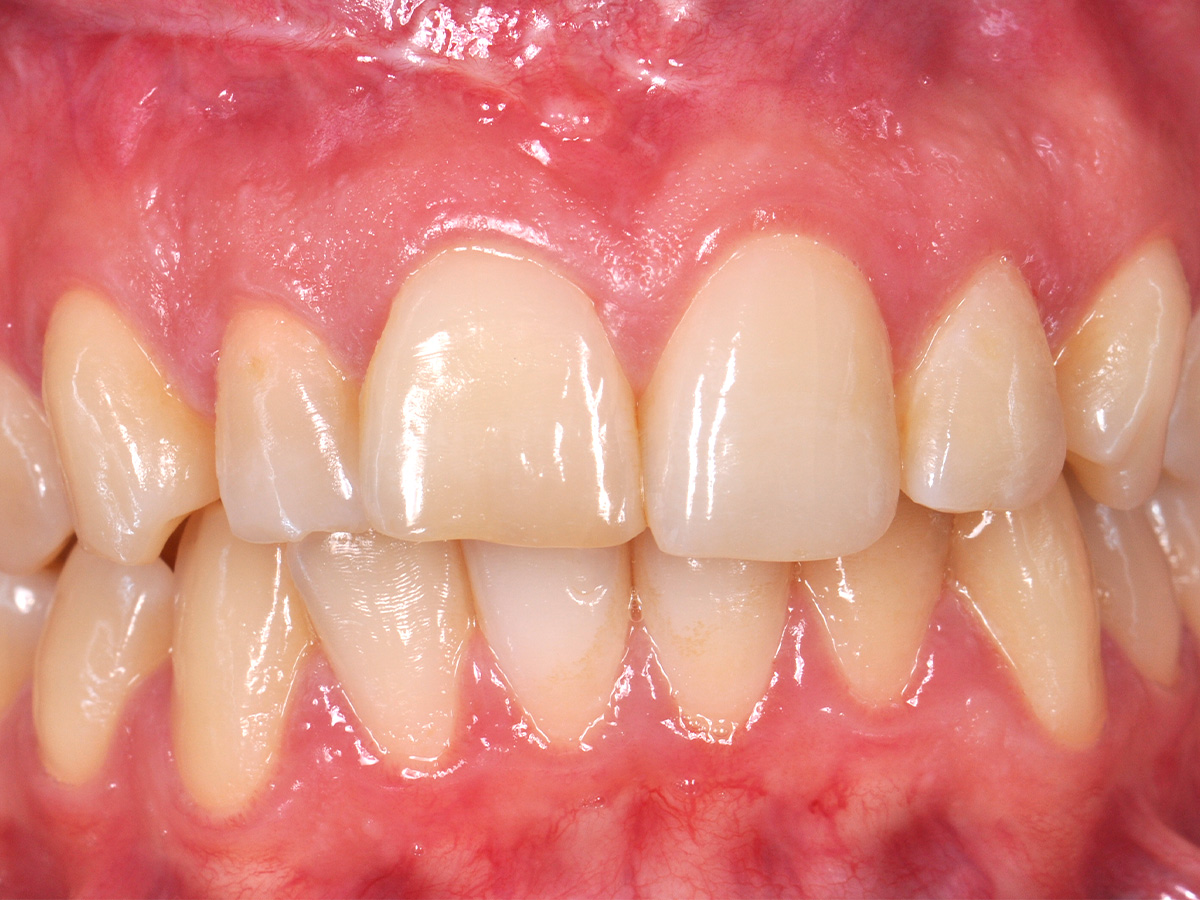

Abbildung 2

Prä-OP: Front nah en face.

Nach einem Zahntrauma im Jugendalter mit anschließender endodontischer Versorgung stellte sich unsere 24-jährige Patientin mit seit einigen Monaten bestehendem, rezidivierendem Druckgefühl und leichten Schmerzen in regio 11 und 12 vor (Abb. 1, 2, 3). Die klinische Untersuchung ergab an Zahn 11 und 12 Lockerungsgrad 1 und, wie zu erwarten, eine negative Sensitivität. Es lag ein leichter Perkussionsschmerz vertikal wie horizontal vor. Die Krone auf Position 11 zeigte eine leichte Verfärbung im Vergleich zu den Nachbarzähnen. Ein OPG ergab eine – in ihrer Ausdehnung nicht sicher zu beurteilende – Aufhellung im Knochenbereich regio 11 und 12 (Abb. 4). Als Nebenbefund waren teilretinierte Zähne 38 und 48 sowie ein vollständig retinierter Zahn 28 als Mikroform nachzuweisen. Ein zusätzlich durchgeführtes DVT zeigte eine große zystische Formation unter Einschluss der Wurzeln 11 und 12, die vom Canalis nasopalatinus bis mesial 13 mit einer kleineren Perforation zum Nasenboden und größeren Perforationen nach vestibulär und palatinal reichte (Abb. 5, 6, 7).